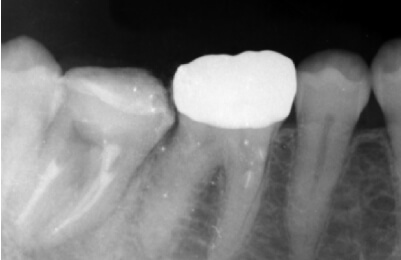

精密根管治療症例紹介

精密根管治療症例

術前

治療中

矢印部が処置されていない

術後

矢印部に大きな骨吸収像

根管を清掃した後

骨の再生が見られる

| 主訴 | 噛むと違和感がある。 レントゲンで根の先に黒い影を指摘された。 |

|---|---|

| 治療期間 | 根管治療3回 補綴治療3回 |

| 治療費 |

(ファイバーコア・ジルコニアクラウン) |

| 治療内容 |

通法の根管治療を行いました。ラバーダム防湿、 マイクロスコープ下で未処置であった根管を発見し処置。 |

| 治療のリスク |

治療直後は反応性に一時的な腫れや痛みが出る可能性があります。 根管治療で改善が見られない場合は外科的根管治療が必要になる場合があります。 |